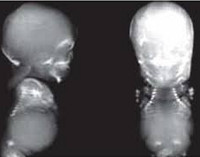

Ахондрогенез. Группа наследственных заболеваний, относящихся к классу тяжелых скелетных дисплазий, часто приводящих к антенатальной смерти или летальному исходу в раннем возрасте. Основным проявлением этих патологий является резкое нарушение процессов окостенения, которое внешне проявляется укорочением конечностей, недоразвитием ребер, грудной клетки, позвоночника. Диагностика производится на основании рентгенологических данных, а также генетических исследований - поиска мутаций в ассоциированных с ахондрогенезом генах. Специфическое лечение отсутствует, возможна только поддерживающая терапия и реанимационные мероприятия.

Постановка диагноза «ахондрогенез» основывается на оценке настоящего статуса пациента, рентгенологических данных, генетических исследований и изучении наследственного анамнеза и гистологического строения хрящей. На рентгенограммах костей обнаруживается укорочение длинных трубчатых костей, нарушения окостенения позвоночного столба, ребер, часто выявляют патологические переломы последних (особенно при ахондрогенезе тип 1а). Снижение оссификации также наблюдается в тазовых костях и на крестце. На метафизах бедренных костей при ахондрогенезе обнаруживаются шипообразные отростки.